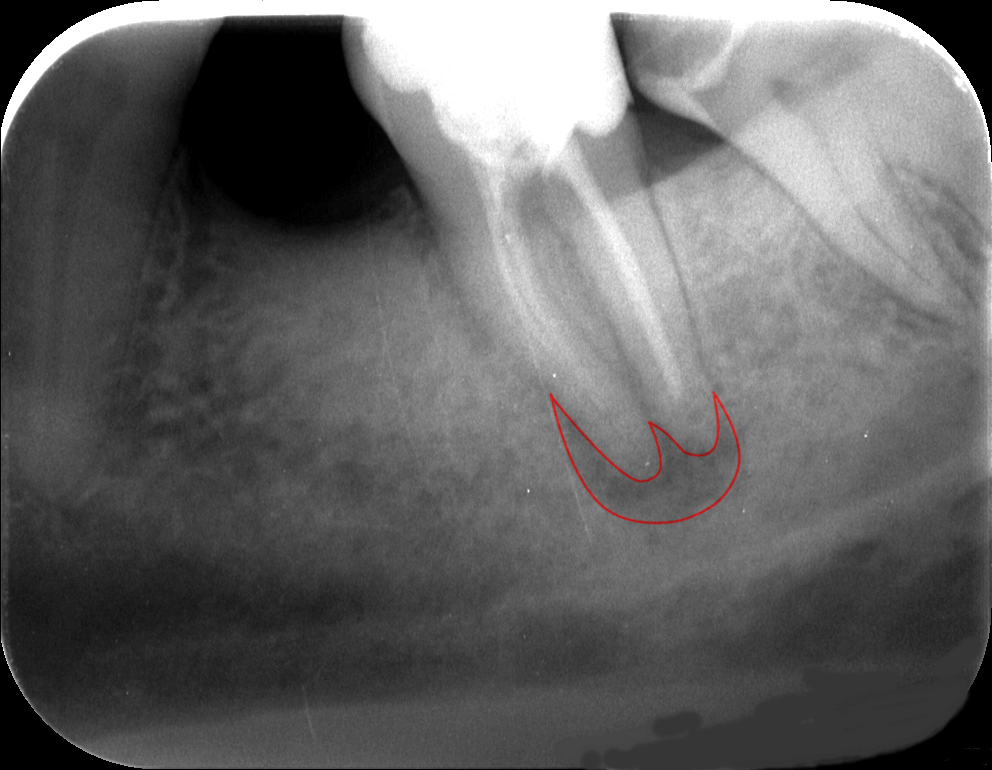

2. Felvétel-képalkotó eljárás

Sima röntgen vagy panorámaröntgen elkészítése mindenképpen javasolt, sőt, CT-felvétel is szóba jöhet. Mindenképpen fontos felmérni, hogy a meglévő fogakat mennyire lehet felhasználni a hagyományos koronához vagy hídhoz. Ezeket a felvételi eljárásokat az Uniklinik tőszomszédságában található saját röntgen- és CT-laborunkban végezzük, vagyis a páciensnek nem kell egy távoli röntgenlabort felkeresnie.

A korona alatt a fog, illetve az íny úgy is megbetegedhet, hogy a páciens nem vagy alig érez fájdalmat. A fogszuvasodás, az ínygyulladás vagy a fogágybetegség következtében azonban egy-kettőre megtelepedhetnek a káros mikrobák akár a mélyebb csontszövetekben is, miközben a beteg ebből (szinte) semmit sem érzékel. A fog és az így között, illetve a korona szélénél esetlegesen feltörő genny sokkal komolyabb betegséget jelezhet, mint gondolnánk. Ezért az első tünetek észlelésekor forduljunk orvoshoz! Ha a korona alatt romlik a fog, nagyon fontos, hogy minél előbb cselekedjünk.

A korona alatt kialakuló betegségeket más tünetek is jelezhetik. Ilyen például ha a korona alatt büdös, kellemetlen szagot, ízt tapasztalunk. Ez a gennyes gyulladás mellett árulkodhat fokozott fogkőképződésről, fogágybetegségről, fogszuvasodásról is. A korona alatt kialakuló különféle betegségek megelőzése érdekében ajánlott minimum évente egyszer ellenőrző vizsgálatot végeztetni a kezelőorvosunkkal.